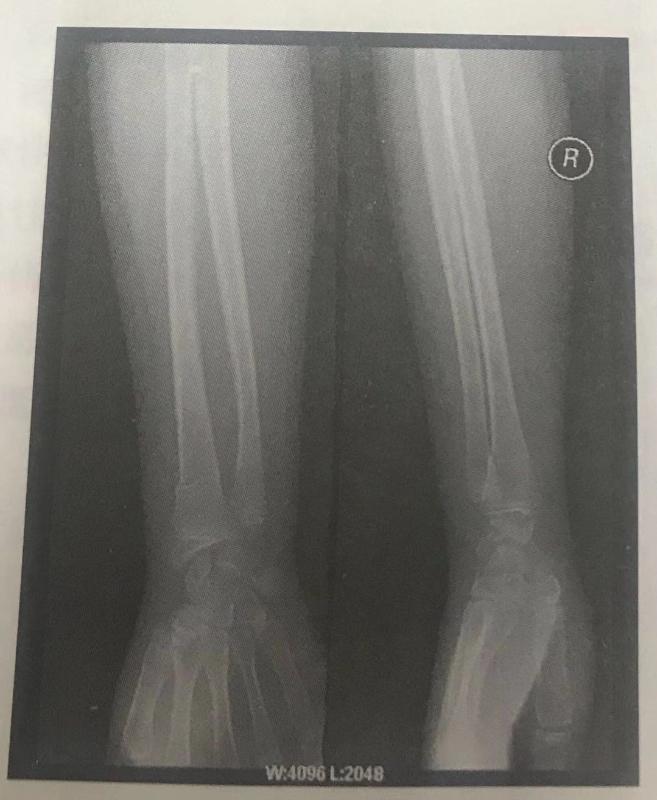

西醫(yī)答辯例題1:根據(jù)下面X線片判斷臨床意義。(5分)

【本題 5 分,建議 1 分鐘內(nèi)完成本題】

【正確答案】 參考答題要點(diǎn):右撓骨遠(yuǎn)端青枝骨折。

【該題針對(duì)“X線片”知識(shí)點(diǎn)進(jìn)行考核】